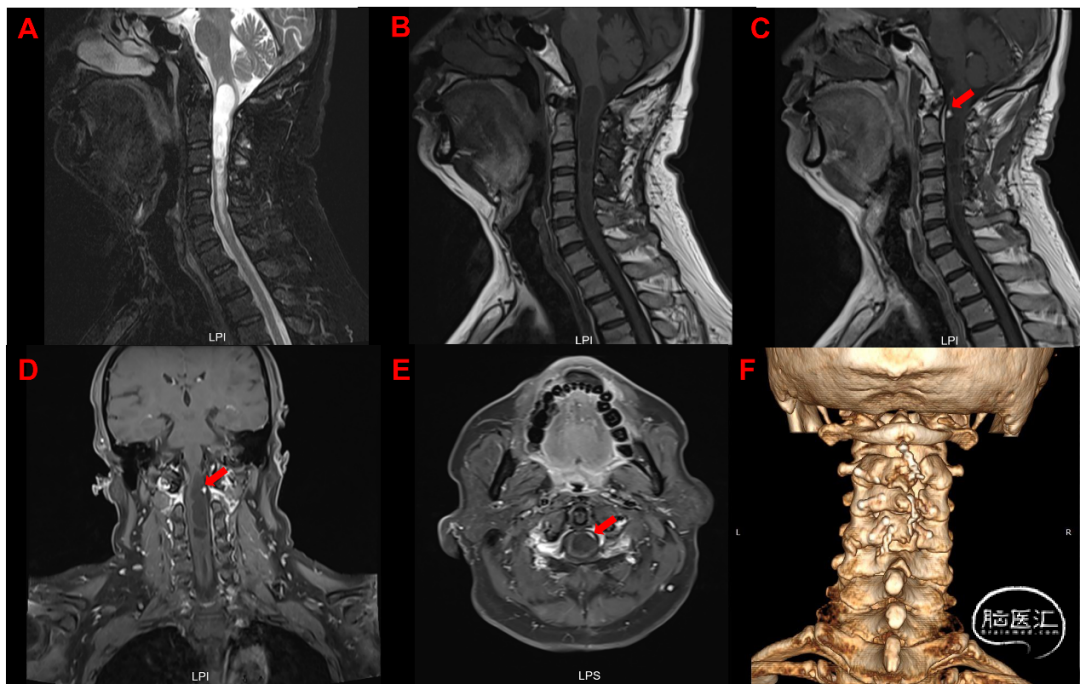

术前检查:我院颈椎增强MRI提示:延髓至颈6水平髓内囊实性病变,增强后提示约颈1水平脊髓腹侧偏左可见明显强化小结节影,首先考虑血管母细胞瘤(图2)。颈椎CT-VRT重建提示:颈髓术后,相应颈椎附件呈术后复位重建改变(图2E)。

患者全麻满意后取俯卧位,消毒铺巾,导航定位,神经电生理监测,以C1-2为中心取约5cm直切口,切开皮肤,剥离双侧椎旁肌肉,暴露C1-2棘突及椎板,磨钻磨除C1后弓及C2左侧椎板上缘,椎板咬钳咬除黄韧带,扩大骨窗,完成椎管减压,剪开硬脊膜悬吊,松解蛛网膜,沿左侧探向脊髓腹侧,于左前方见血管性结节,上下相邻血管扩张明显,提示血供丰富,质软,形态不规则,约1cm×1cm×1cm大小,基底嵌入髓内,外生型生长偏向左侧,考虑为血管母细胞瘤。行术中荧光造影可见肿瘤上方有脊髓腹侧发出的血管进入肿瘤,依据造影结果先电凝阻断供血血管,悉心保护周围正常脊髓,沿病灶与脊髓界面从软膜下分离边界后,全切肿瘤。术区严密止血,松解粘连神经根。神经电生理监测提示双下肢MEP可及,与术前对照相仿。取6-0 proline镜下严密硬脊膜,硬膜外止血后逐层缝合肌肉及皮肤,手术结束,术中出血约20ml。